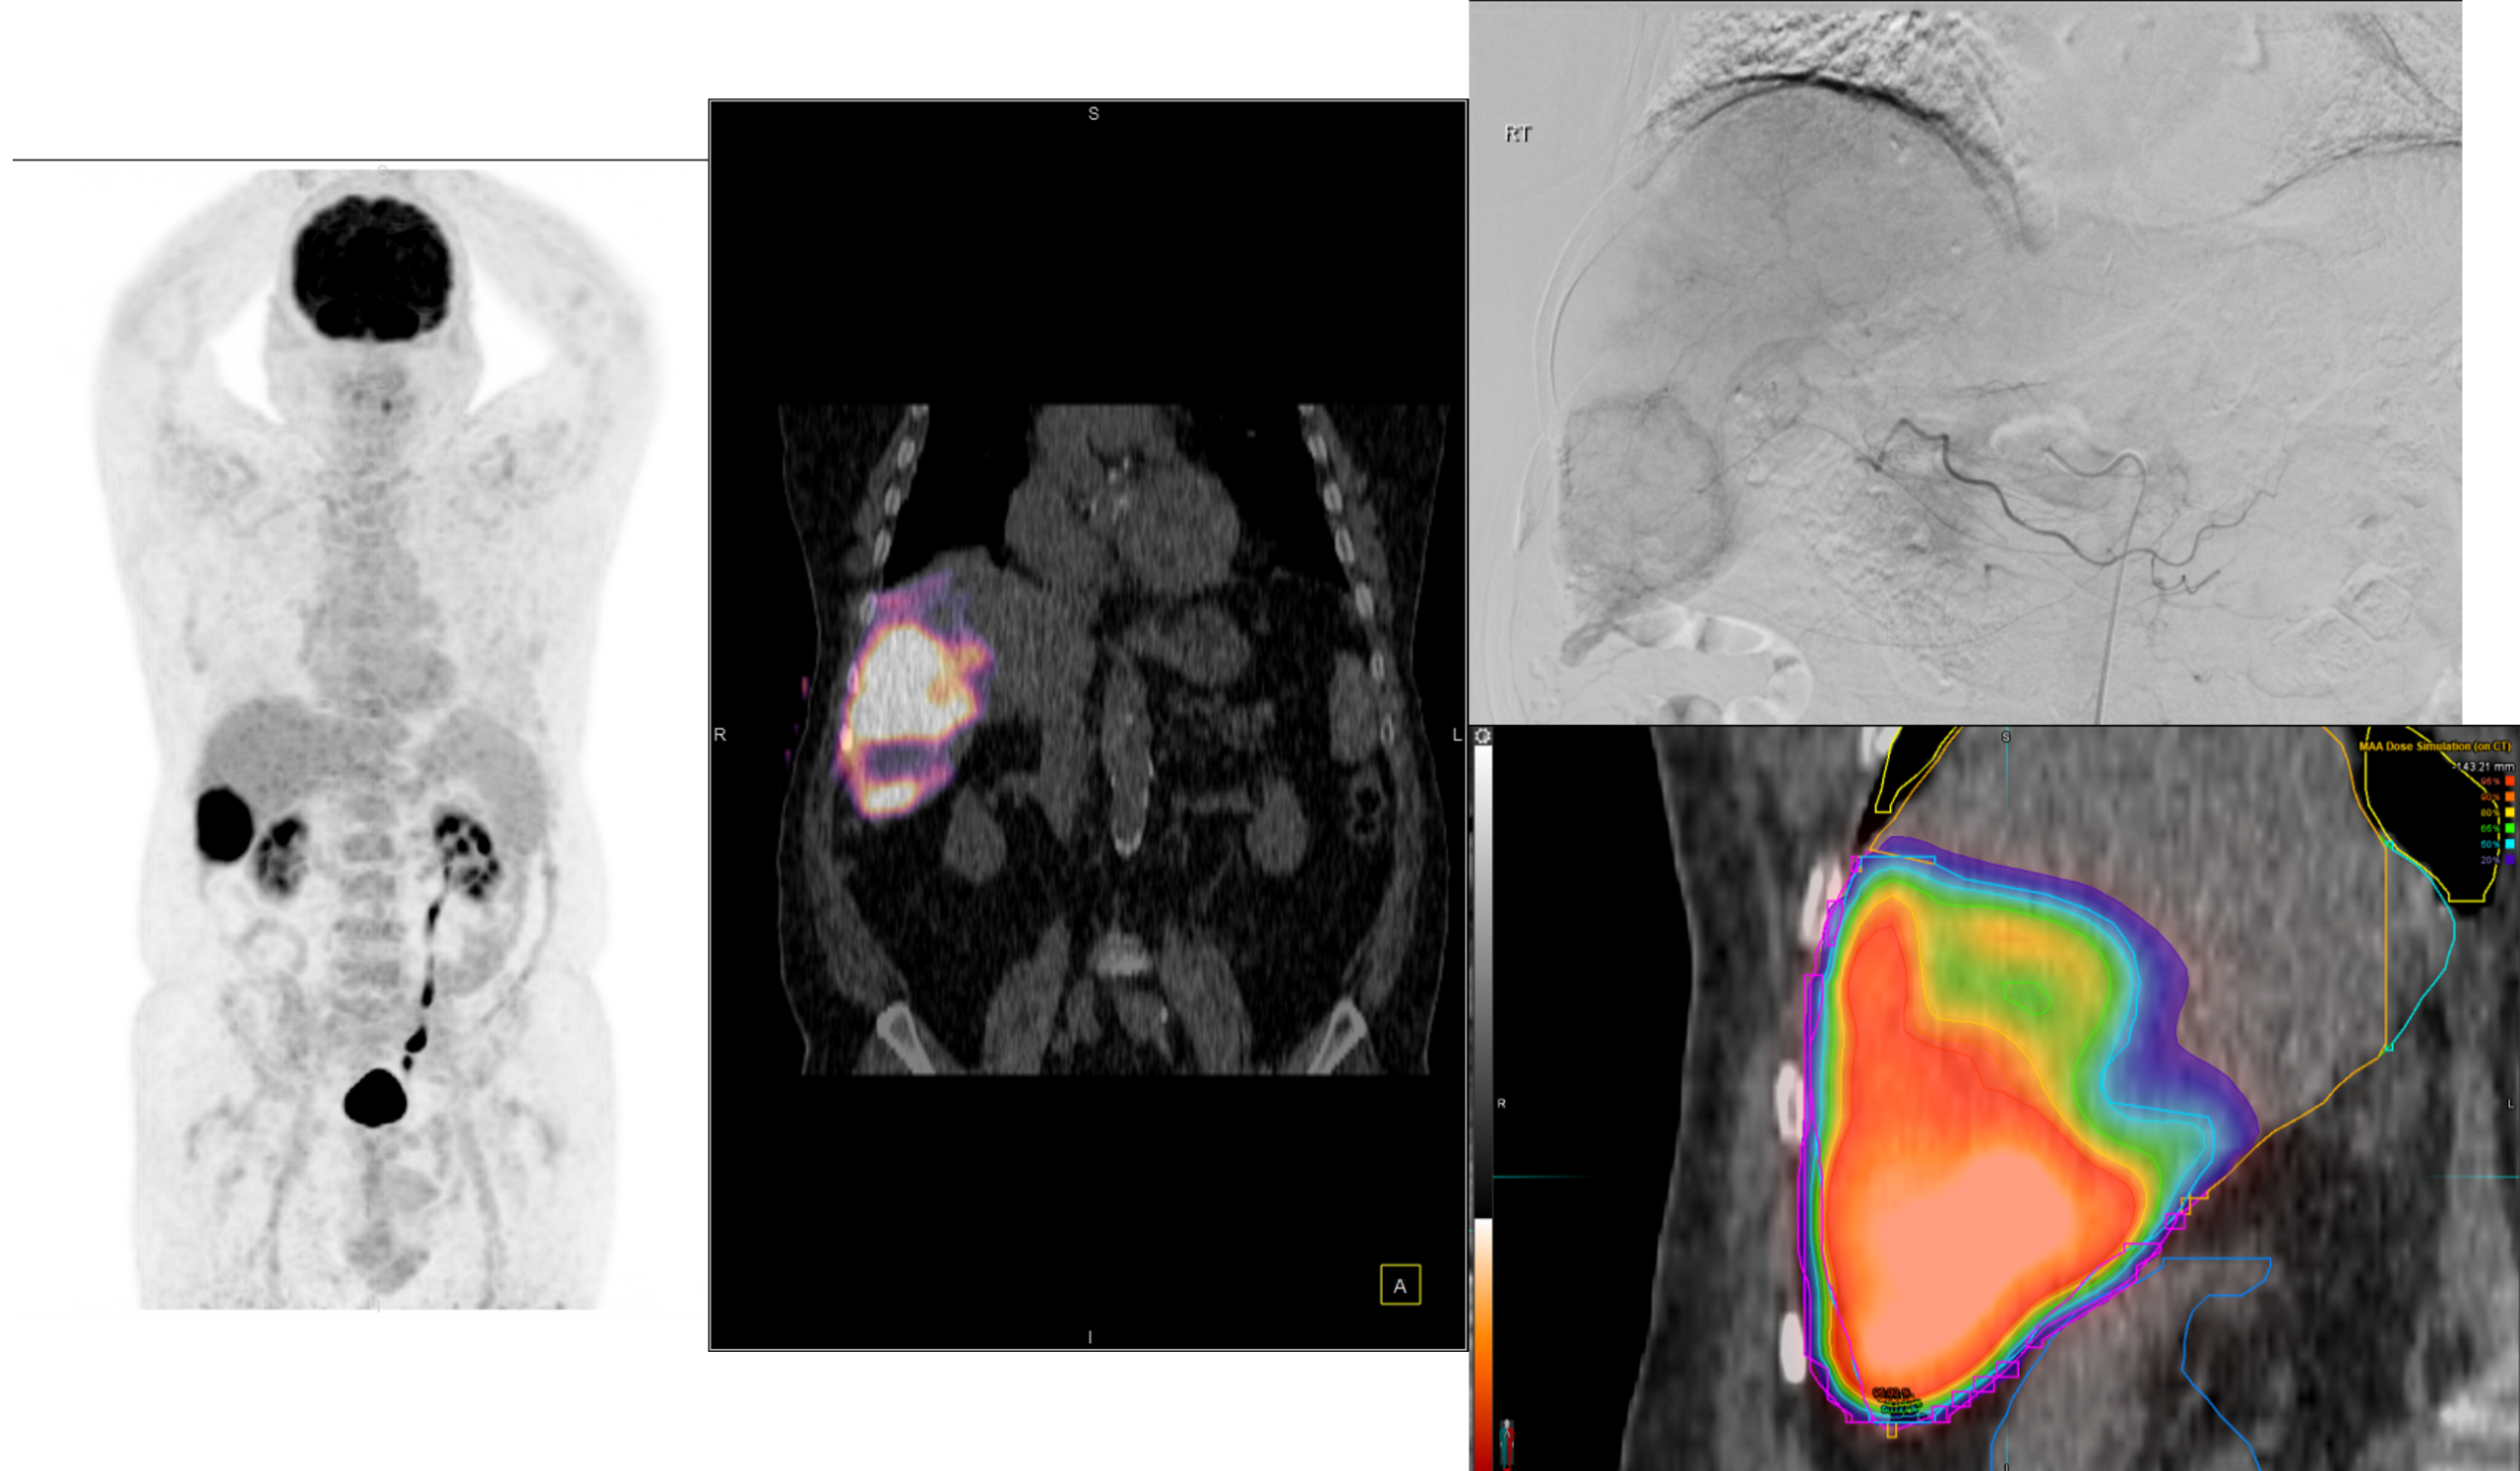

Η θεραπεία με Ύτριο-90 SIR-Spheres (Y-90) αποτελεί μια εξειδικευμένη τεχνική εκλεκτικού ενδοαρτηριακού εμβολισμού, η οποία στοχεύει αποκλειστικά τον όγκο μέσω των ηπατικών αγγείων, επιτρέποντας την εναπόθεση σωματιδίων που εκπέμπουν ραδιενέργεια τοπικά με ελάχιστη ακτινική επιβάρυνση στους υγιείς ιστούς. Η διαδικασία περιλαμβάνει λεπτομερή προθεραπευτικό αγγειογραφικό σχεδιασμό με αξιολόγηση της αγγειακής ανατομίας και χορήγηση ενός ιχνηθέτη για την ανίχνευση τυχόν διαφυγής (πχ. lung shunt), εξασφαλίζοντας μέγιστη ασφάλεια και εξατομίκευση. Η επιλογή της δόσης γίνεται πλέον με σύγχρονα υπολογιστικά μοντέλα δοσιμετρίας και εξειδικευμένα λογισμικά (όπως MIM ή SIR-TeX platform), τα οποία επιτρέπουν ακριβή αποτύπωση του όγκου της νόσου στο ήπαρ, υπολογισμό του πραγματικού tumor burden και εκτίμηση της απορροφούμενης δόσης τόσο στον όγκο όσο και στο υγιές ηπατικό παρέγχυμα. Μετά τη θεραπεία, πραγματοποιείται έλεγχος κατανομής της ακτινοβολίας (μέσω Bremsstrahlung SPECT/CT ή PET/CT), ενώ ακολουθεί στενή απεικονιστική και κλινική παρακολούθηση για την αξιολόγηση της ανταπόκρισης, την εκτίμηση τυχόν τοξικοτήτων και τον σχεδιασμό επόμενων βημάτων στην ογκολογική στρατηγική του ασθενούς. Πρόκειται για μια ιδιαίτερα αποτελεσματική θεραπευτική επιλογή σε πρωτοπαθείς ηπατικούς όγκους και σε ηπατικές μεταστάσεις, ειδικά όταν οι συμβατικές θεραπείες έχουν περιορισμένη αποτελεσματικότητα ή δεν είναι πλέον εφικτές.